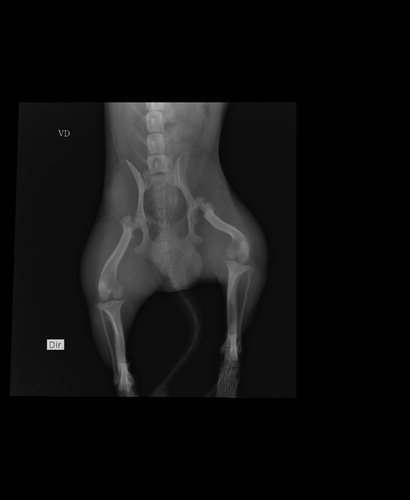

No dia 05/11/2025, o Romeo, meu cachorrinho, foi atropelado por um motoqueiro que infelizmente não prestou socorro e foi embora. 😢Ele machucou seriamente a patinha e precisa passar por exames, tomar remédios e fazer uma cirurgia no fêmur para conseguir andar sem dor e ter qualidade de vida novamente.